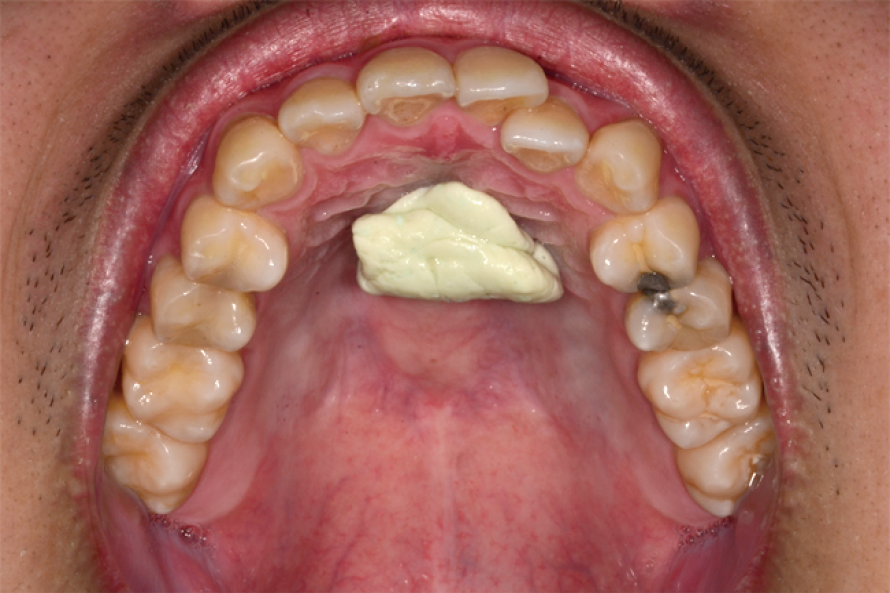

• 用後牙咀嚼口香糖(建議無糖口香糖),在用舌頭將咀嚼過的口香糖滾動至舌尖處(圖一)。

• 利用舌頭往上舉的力量把口香糖推到上顎穹窿的位置(圖二),訓練咬合與吞嚥的動作,保持用舌頭讓口香糖壓在上顎穹窿處(圖三),讓口香糖完全的經過舌頭的壓力平鋪到上顎穹窿處(圖四)。